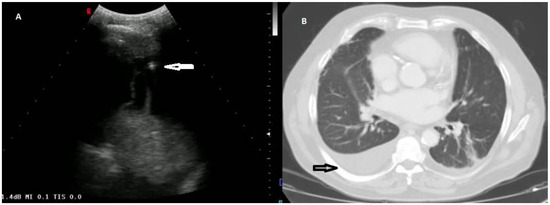

Figure 5. (A) TUS scan showing a complex nonseptated effusion with consensual parenchymal atelectasis. The tip of the needle during TUS-guided thoracentesis with a multifrequency convex probe (3.5 MHz) is highlighted by a white arrow. (B) The corresponding CT scan shows an extensive apico-parieto-basal pleural effusion of greater right expression (black arrow) with consensual lower lobe atelectasis. A bilateral thickening of interlobular septa and some right ground-glass opacities with partial sparing of the lung periphery are also present (congestive heart failure).

Six of the 33 effusions (18.18%) presented by patients diagnosed with heart failure were classified as exudates. Such effusions presented a complex nonseptated appearance on TUS examination (Figure 5).

As part of a standard routine protocol, further diagnostic investigations (including chemical, microbiological, and cytological studies) were carried out on the pleural fluid. According to this protocol, the first step consisted of the analysis of pleural fluid for pleural lactate dehydrogenase (LDH) and proteins in order to establish its exudative or transudative nature according to Light’s criteria [5]. Exudative effusions have a higher protein concentration (>30 g/L) resulting from an increased capillary permeability related to several local inflammatory processes, including pneumonia and cancer. On the other hand, transudative effusions result from imbalances in hydrostatic and oncotic forces and are caused by a limited number of recognized clinical conditions such as heart failure [28,29]. However, a certain percentage of initially transudative effusions can be classified as exudates by Light’s criteria, as diuretic therapy increases the total protein and lactate dehydrogenase concentrations in pleural transudates due to heart failure and chronic transudative effusions naturally tend to form fibrin septa over time [30]. This occurrence was confirmed also in our study, in which 18.18% of the effusions presented by patients diagnosed with heart failure were classified as an exudate. Such effusions also showed a complex nonseptated appearance on TUS examination.